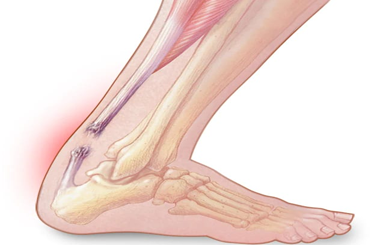

Arthroscopy ligament surgery

This advanced technique involves the use of a small, pencil-sized instrument called an arthroscope.Arthroscopic ligament surgery is a minimally invasive procedure used to diagnose and treat injuries to ligaments within a joint, commonly the knee or shoulder. The procedure is typically performed under general anesthesia, though regional anesthesia might be used for some cases.